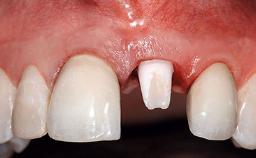

A 30-year-old patient presented at our clinic with a chief complaint of pain in her endodontically treated right maxillary central incisor (tooth 11) with a post-and-core and a fixed single crown. She had a very high lip line, a medium to thin soft-tissue phenotype, and a medium scalloped gingival contour. She also had high esthetic expectations because of her young age and beautiful smile. However, her expectations were realistic and she understood the risks of the treatment. At the initial clinical examination there was a slight mobility of tooth 11; no fistula was observed. The patient also had a single crown on the adjacent tooth 21. Both restorations were old and esthetically deficient. A digital periapical radiograph showed a very small periapical radiolucency, a thick intraradicular post, and no separation between root fragments.